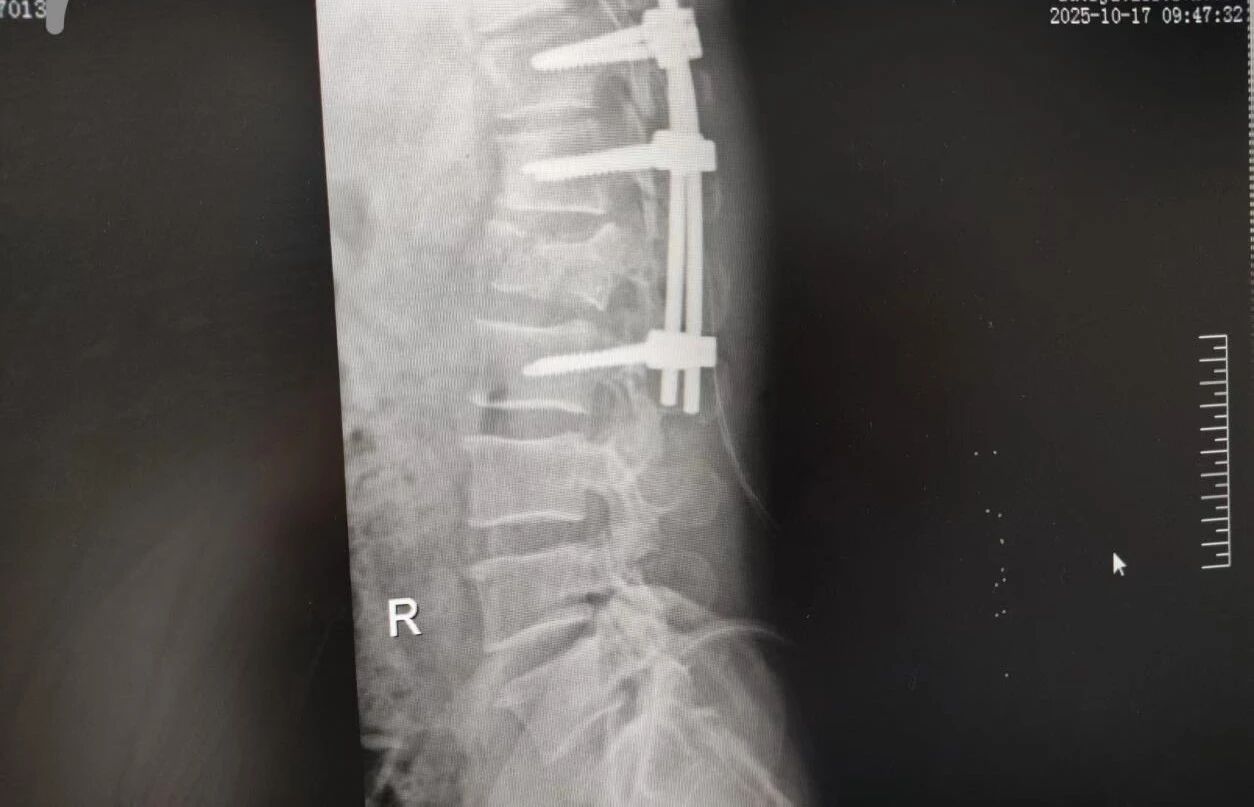

63 歲的王先生(化名)高空作業(yè)時不慎墜落,由漯河市中醫(yī)院急診科緊急接診。入院時,他已生命垂危,初步檢查結果觸目驚心:腰 1 椎爆裂性骨折(脊柱嚴重損傷,隨時面臨永久性癱瘓風險)、多發(fā)肋骨骨折伴血氣胸與肺挫傷(胸腔 “堡壘” 重創(chuàng),呼吸功能幾近崩潰)。任一傷情皆足以致命,多重重創(chuàng)更讓其陷入生死絕境。

針對腰椎傷情,骨科竇志剛醫(yī)生團隊緊急開展腰 1 椎體爆裂性骨折切開復位內(nèi)固定術 + 椎板切除減壓術。手術室、麻醉科無縫銜接開通綠色通道,手術團隊快速就位,術后患者下肢活動恢復自如。